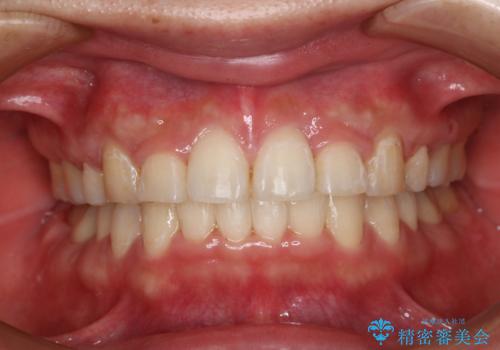

- 治療計画

- 前歯のがたつきが気になるとご相談にいらした方です。当初は前歯の部分矯正をご希望されていましたが、全体的に整えることで審美的、機能的な歯並びとなりました。

当初は上顎前歯のみの部分矯正をご希望されていましたが、部分的に前歯のみを並べると出っ歯感がつよくなり、食事もしづらくなる可能性をお伝えしました。全顎的な矯正治療により、審美的、機能的な歯並びとなりました。